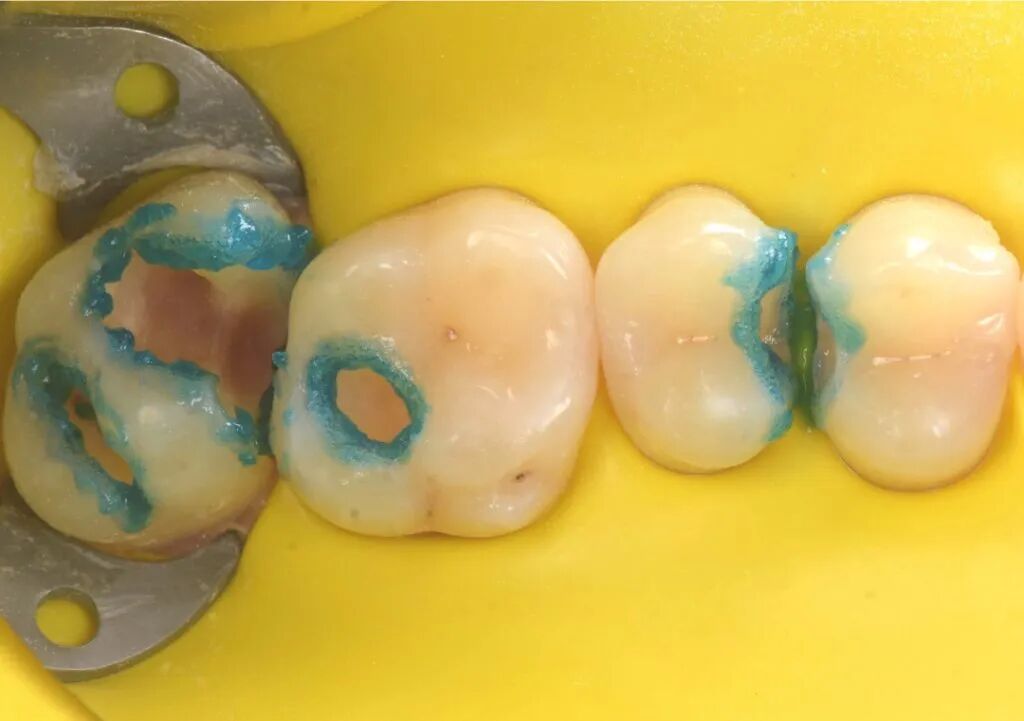

图11. 光固化垫底材料置于27窝洞最深处。

图12. 光固化20秒。

图13. 垫底后准备充填修复。